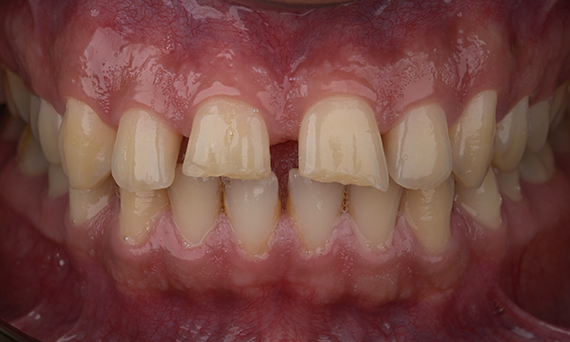

Amélogenèse imparfaite

Restauration complète de la bouche avec 28 restaurations tout céramique

Un cas particulier et prolongé de malocclusion squelettique de classe II et d’amélogenèse imparfaite généralisée chez un adolescent a été référé pour une réhabilitation prothétique. L’objectif du traitement était de préparer la structure dentaire restante, d’éliminer les contre-dépouilles et de faire de la place pour des couronnes entièrement en céramique couvrant toute la dentine et simulant l’émail perdu.

Avant : Situation initiale avant le traitement orthodontie.

Après : Résultat final, 1 semaine après l’opération.